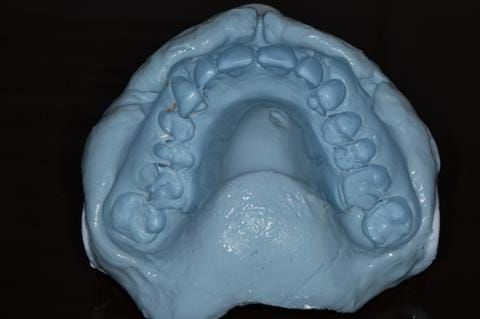

Provision of a maxillary cobalt chromium based partial denture/protective occlusal splint in a heavily restored dentition

- Extract the upper 2-2 teeth and replace with an interim acrylic based partial denture. Reline the interim denture over 9 - 12 months, replacing with a definitive cobalt chromium based partial denture. The definitive denture would ideally be designed as an occlusal protective splint to reduce the the potential for mechanical wear and breakages of the moderately/heavily restored maxillary dentition. In addition, should further upper teeth require extraction they could be added on to the denture cobalt chromium framework - therefore a new prosthesis would not be required as future teeth are lost. This option would produce an excellent aesthetic outcome. This is the option the patient chose to have.

Following consultation and second discussion appointment the patient chose to have option 3 namely, a maxillary cobalt chromium based partial denture/protective occlusal splint. The clinical situation and treatment process is shown in detail below with photographs. The patient was successfully rehabilitated with this and her quality of life considerably improved. The clinical work was provided by Finlay and the technical work by Rowan.